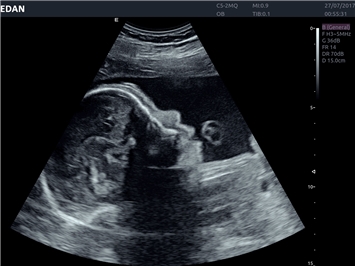

EDAN Acclarix LX4

Расширьте свои представления. Использование усовершенствованной платформой Acclarix система LX4 обеспечивает непревзойденную четкость изображений и интеллектуальный рабочий процесс для всех пользователей, являясь при этом наиболее экономичным решением.

EDAN Acclarix LX4 представляет собой инновационную ультразвуковую систему, построенную на усовершенствованной платформе Acclarix. Сочетание высокого качества визуализации с интеллектуальным рабочим процессом делает эту систему оптимальным выбором для клиник, ценящих эффективность и экономичность.

• 3D/4D-визуализация с автоматическим редактированием объема (eFace)

• Автоматизированные измерения в акушерстве

• Акушерства и гинекологии